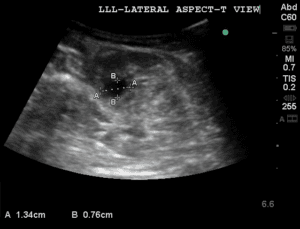

A vascular lab performed duplex ultrasound was ordered to confirm our bedside findings and revealed extensive DVT in the left lower extremity including the distal external iliac vein, CFV, proximal deep femoral vein, proximal-to-distal FV, as well as acute superficial venous thrombosis in the great saphenous vein at the level of the saphenous-femoral junction and proximal thigh (Figure 3).

Figure 3. A vascular-performed duplex ultrasound revealed acute non-compressible deep vein thrombosis in the left lower extremity involving (A) the left superficial femoral vein; (B) the left deep femoral vein; (C) the left external iliac vein; (D) the left common femoral vein.